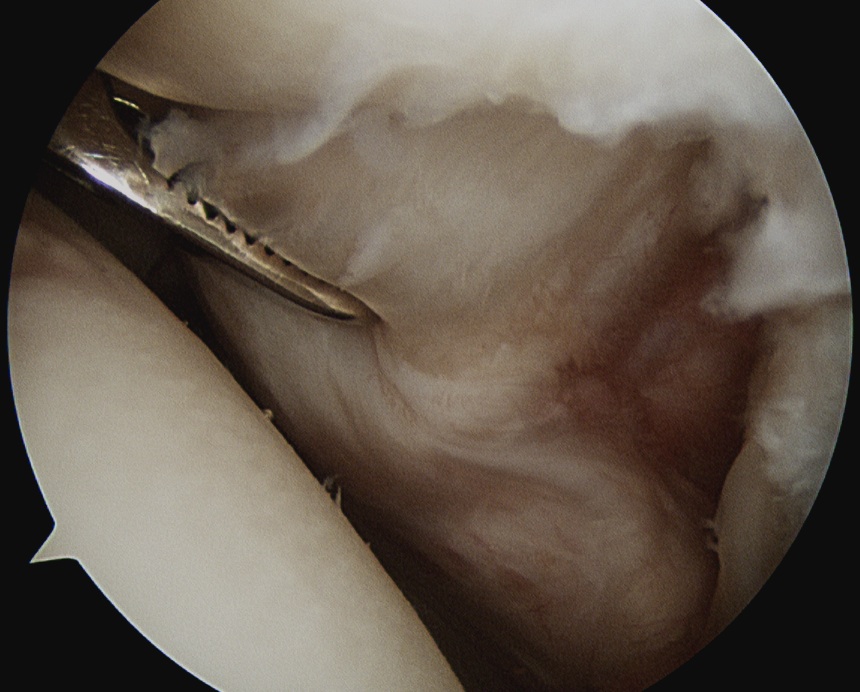

Full thickness tear of subscapularis off insertion revealed with grasper

Comma Sign

Comma sign

- medially retracted subscapularis tear

- exposes the superior insertion of superior glenohumeral ligament / coracohumeral ligament

Full thickness retracted subscapularis tear with comma sign

Full thickness completely retracted subscapularis, loss of rotator interval and comma sign

Full thickness completely retracted subscapularis, loss of rotator interval and comma sign